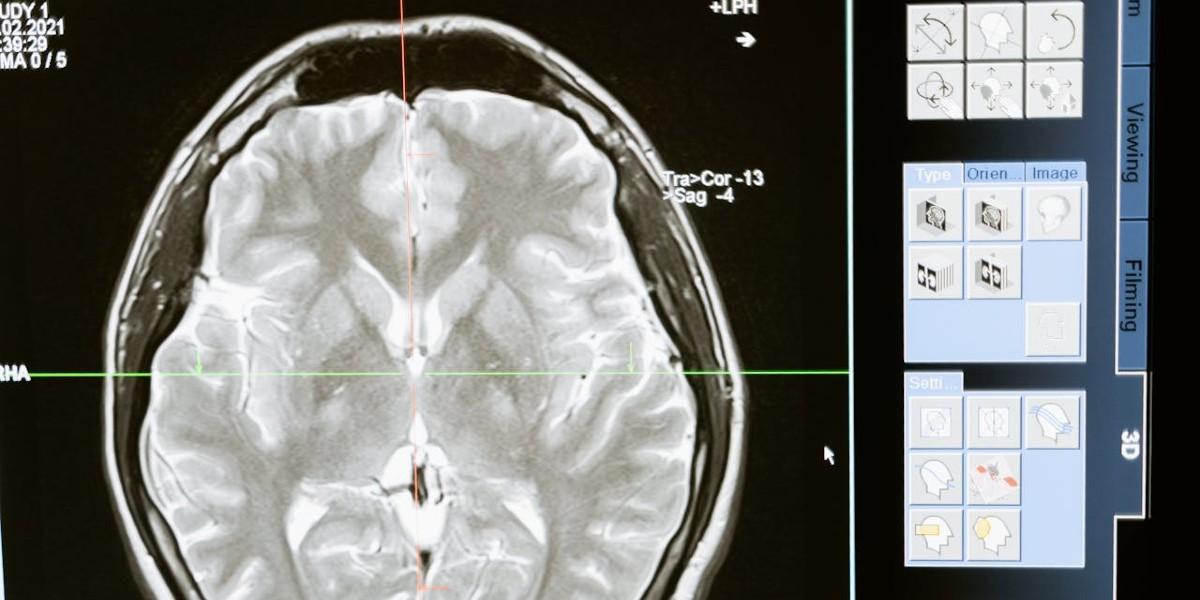

Rödvin och choklad minskar risken för demens

En kost rik på flavonoider, växtföreningar som finns i te, rödvin, bär och mörk choklad, kan avsevärt minska risken för demens. Forskare tror att flavonoider kan ha en skyddande effekt på hjärnceller och hjälpa till att blockera uppbyggnaden av beta-amyloidplack, som är ett kännetecken för Alzheimers, det rapporterar Daily Mail. Under sex år analyserade forskare …